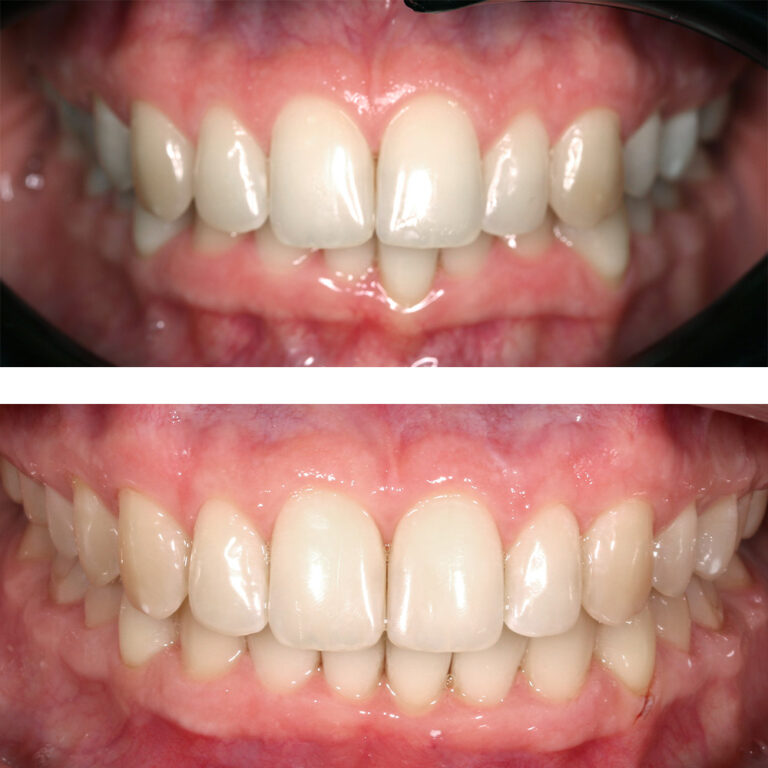

Кейс 13

Булгач (Мочалова) Галина Игоревна

Количество кап ВЧ 19

Количество кап НЧ 24

ДО

ПОСЛЕ